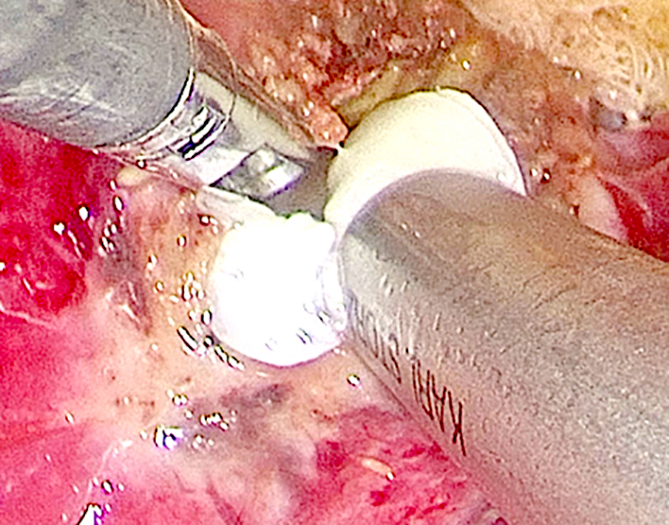

Матеріали та методи. Лапароскопічна ехінококектомія (напівзакритий варіант) виконана пацієнтці 37-ми років з рецидивною ехінококовою кістою діаметром 6 см, локалізованою в верхньому полюсі селезінки і частково інтрапаренхіматозно. Під час операції використовували 4 троакари: два 10 мм і два 5 мм. Після аспірації хітинових оболонок за допомогою 10 мм тубуса відсмоктувача (з високим розрідженням) порожнину дренували двома поліхлорвініловими трубками з герметизацією отвору фіброзної капсули прошиванням.

Результати досліджень та їх обговорення. Операція тривала 100 хвилин, пацієнтку виписали зі стаціонару на 4-й день післяопераційного періоду з добре взаємно функціонуючими дренажами. Надалі пацієнтці проводили промивання залишкової порожнини розчином бетадину 1:100 в амбулаторному порядку щодня. Післяопераційних ускладнень не було.